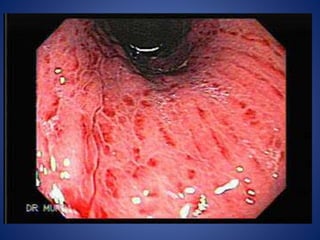

I. REFLUX OESOPHAGITIS

• The disorder may be defined as damage to the

esophageal mucosa due to reflux of gastric contents.

• Etiology: Increased reflux of gastric contents into the

esophagus from reduced pressure in the lower

oesophageal sphincter and an increased number of

transient relaxation of the sphincter are the main

factors in the development of reflux esophagitis.